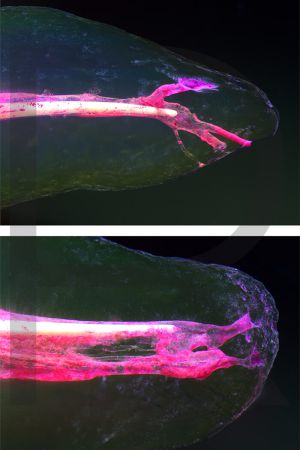

Bildauswahl mit schwebender Aufhängung

Sie haben hier die Möglichkeit, besondere Arbeiten

(© Dr. Holm Reuver) für Ihre Praxis zu erwerben.

Bitte wählen Sie aus klassischen Varianten, Pop Art, Collagen oder Mehrfach-Varianten.

- Foto hinter 3mm Acrylglas, rahmenlos

- hochwertige, unsichtbare Aufhängung, "schwebend“

- Hoher UV-Schutz für lang anhaltend strahlende Farben

- Bruchsicher und leichter als Glas

- Beeindruckende Farben und brilliante Tiefenwirkung

- Druck erfolgt ohne Wasserzeichen

- Bildgröße: 90 x 60 cm, Hochformat

-

Preis: 490,00 Eurozuzüglich 16,90 Euro Versand & Porto innerhalb Deutschlands, weiterer Versand auf Anfrage

Wenn Sie Interesse an den Fotos transparenter Zahnpräparate haben, bieten wir hier die Möglichkeit einige Versionen als Acrylbilder (alle Detailinformationen zu Größe und Preis siehe obige Auswahl) zu bestellen.

Die Bilder sind nicht nur zur Praxisverschönerung geeignet sondern auch eine wertvolle Unterstützung bei der Patientenberatung vor endodontischen Behandlungen.